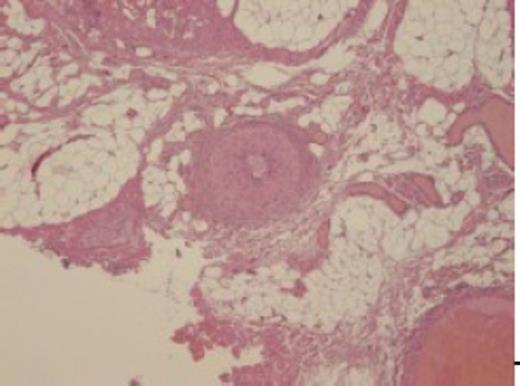

Histopathological findings. Note that the lesion is composed of lobules of mature fatty tissue with various sized vessels

In order to adequately cover the excised region, we then elevated the skin flap. For the upper area, the bilobed flap was designed at the left buttock and positioned over the area of the defect. For the middle area, the remaining lateral-based skin lesion flap was restored. To close the wound under slight tension, the baggy medial skin lesion was trimmed to avoid creating dead space. For the lower area, the V-Y advancement flap was designed. In total, the operative time was 6 h 55 min. Total bleeding amounted to 1914 mL, and therefore, a blood transfusion was given. The pathological findings revealed partial lipohyperplasia with venous malformations (Fig. 2).